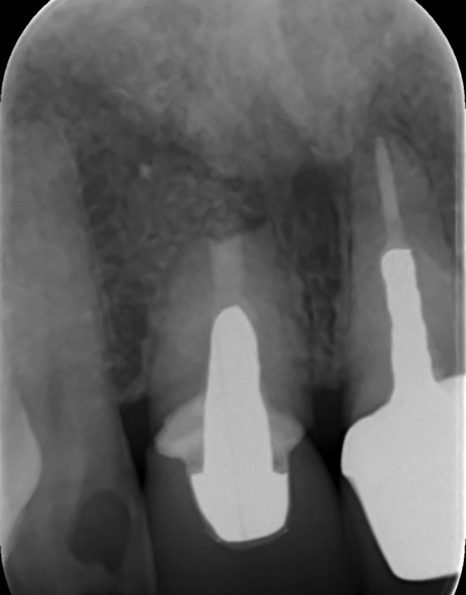

Case 26 – Endodontics

Repeat apicectomy with grafting